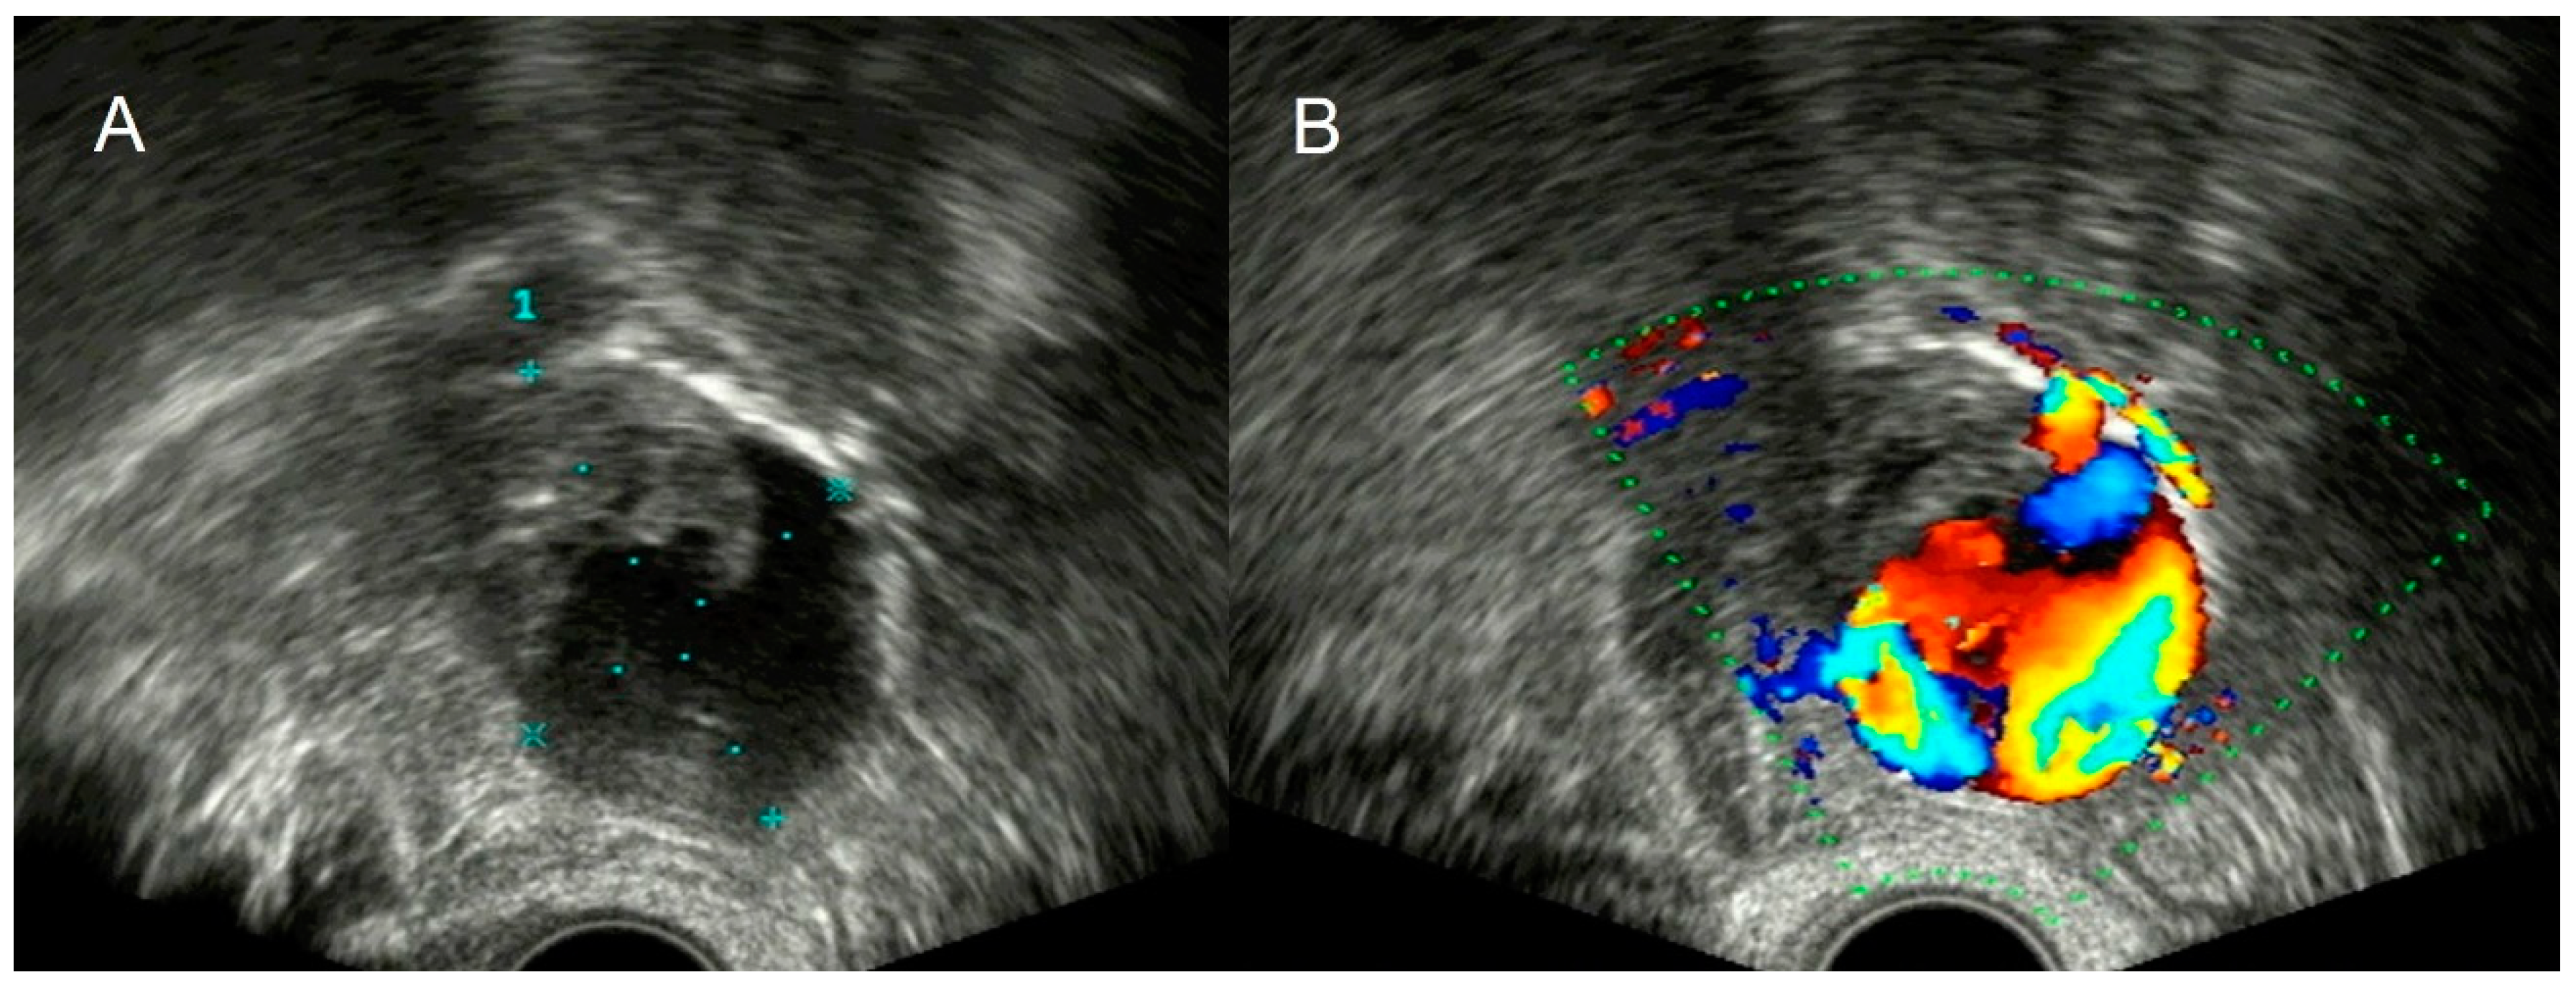

4.2. Thrombosis